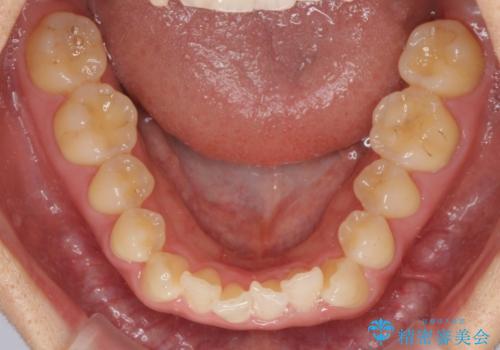

- 上下前歯のデコボコと銀歯のブリッジを気にして来院された患者様です。

矯正治療中に上下前歯が接触しない時期があり、咬み合わせ改善のために期間がかかるのではないかと懸念されましたが、結果的には補綴治療も含めて1年以内の短期間で終えることができました。